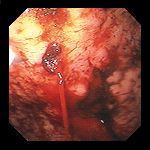

Gastroscopy. Green arrows: orifice of the gastrocolic fistula (Courtesy Dr. V. Penopoulos)